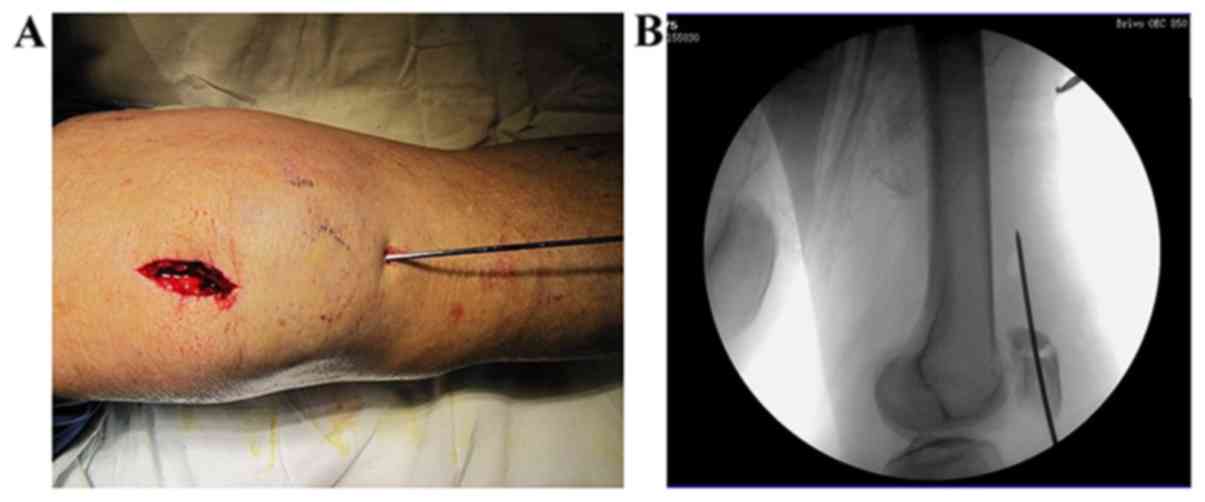

Figure 4.

Fracture reduction and temporary fixation. (A) A K-wire for temporary fixation following the reduction. (B) A C-arm fluoroscopy was used to confirm the anatomical reduction of the articular surface.

If the minor transverse fracture fragment was at the proximal end and the major fragment was at the distal end of the patella (Fig. 2), the site of the proximal fragment would be confirmed and a ~3 cm longitudinal midline incision would be made from the proximal end of the patella down to the lower side of the proximal fragment (Fig. 3). The incision was from the skin to the prepatellar fascia. The soft tissues were pulled downwardto expose the fracture line. Any hematomas and traumatic bone debris were removed, and the articular cavity was washed with normal saline solution. Manipulative reduction was made with the assistance of two towel clamps applied percutaneously. During the reduction procedure, the knee joint was flexed and extended several times, and the fragments were squeezed and pressed against to the femoral condyle to facilitate the reduction of the articular surface. A K-wire was then drilled superiorly and percutaneously into the patella from the lower side of the apex for temporary fixation following the reduction (Fig. 4A). A C-arm fluoroscopy was used to confirm the anatomical reduction of the articular surface (Fig. 4B), and then the prepatellar fascia was sutured.